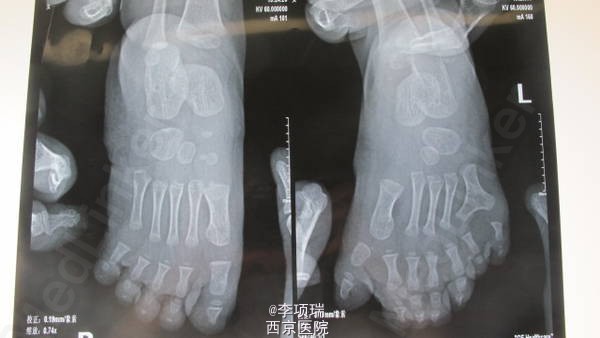

患儿,女,2岁,左足7个趾头伴并趾。

左足7个趾头伴并趾

第二趾切除,第一趾复位后跖骨腓侧契形截骨克氏针固定,第7趾切除,第6趾 跖骨契形截骨克氏针固定。

术后1月拔针,现术后1个半月,足背瘢痕有点增生,其他均好。并趾拟3个月后二期手术。